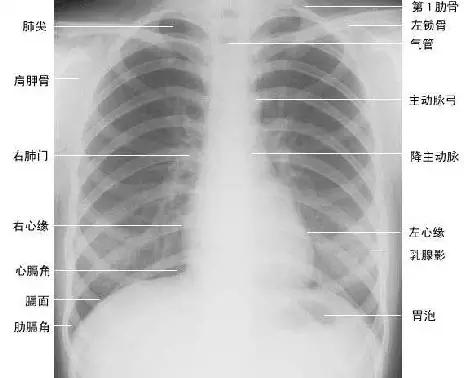

临床拍标准的胸部正位片其实是后前位片,如上图

正常胸部后前位片